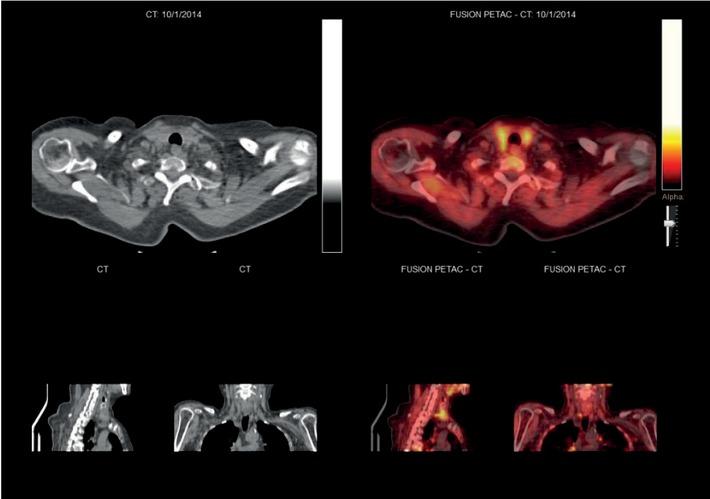

Figure 1

Figure 2

Figure 3

Figure 4